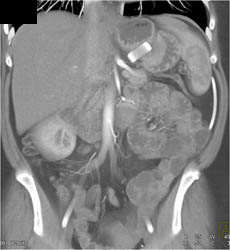

Diagnosis

GIST Tumor